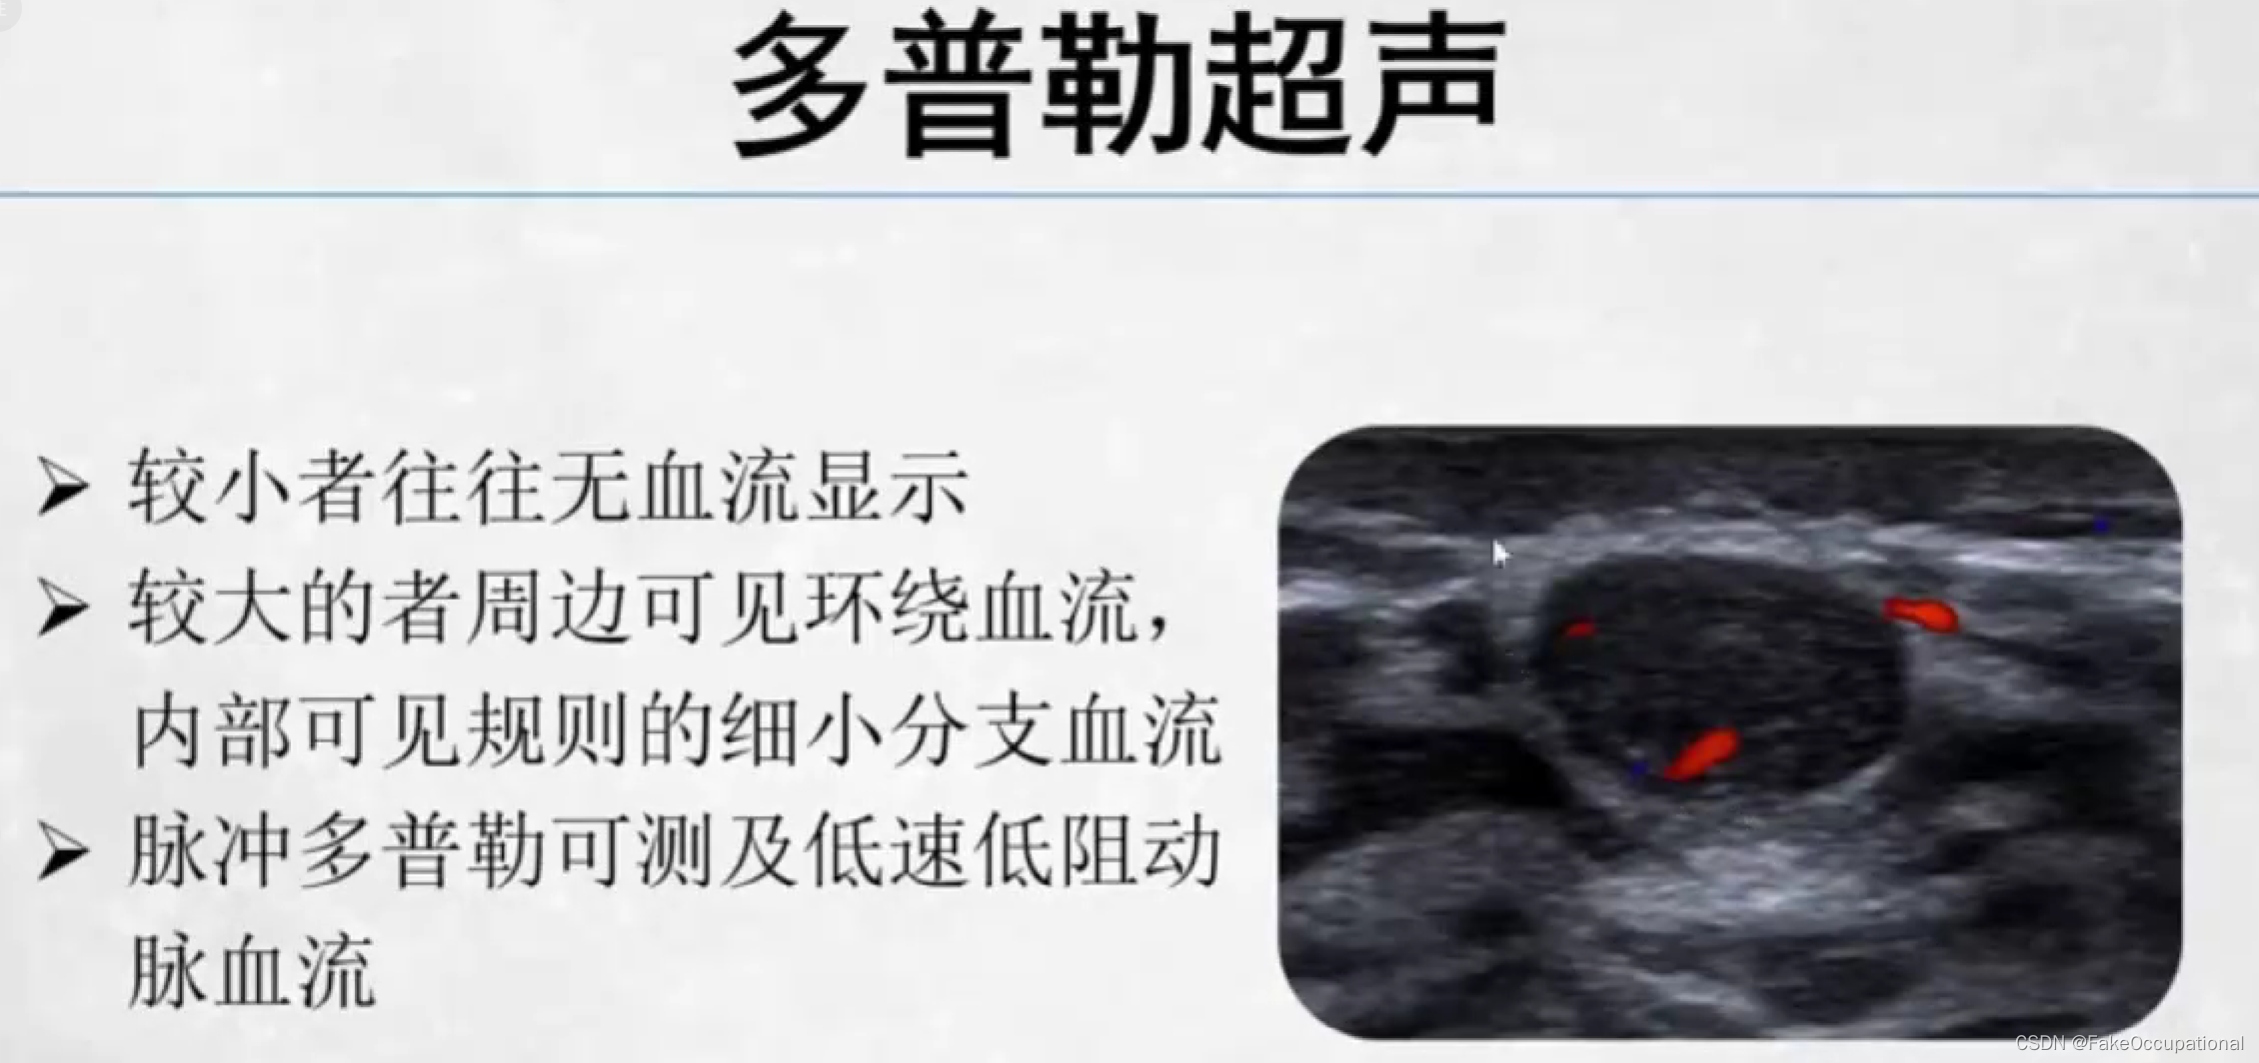

乳腺纤维腺瘤

乳腺纤维瘤 (breast fibroadenoma)

最常见的乳房良性肿瘤,约占乳腺肿瘤的10%

与女性雌激素刺激有关

常见于生育年龄的妇女,特别是30岁以下的女性

无痛、实性、边界清楚、生长缓慢的孤立性结节,触之可移动部分可在同侧或双侧、同时或不同时发生多发性结节